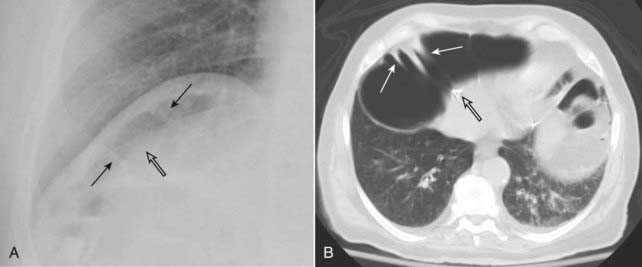

Figure 15-4 Normal left hemidiaphragm (A) and free air under hemidiaphragm (B).

Close-up views of the left upper quadrant demonstrate the difficulty in recognizing free air beneath the left hemidiaphragm because of the normal location of gas-containing structures such as the stomach (S) and splenic flexure (SF). There is no free air seen in (A) but the other patient (B) does have a crescent of free air (solid white arrows). It is easier to recognize free air beneath the right hemidiaphragm because there is usually no air present above the liver on the right side.